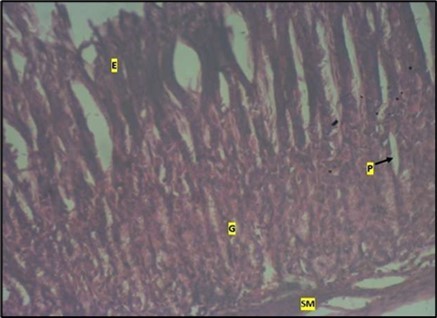

Micrographs of The Stomach

Figure 8.control plate showing gastric pits with goblets cells (g). Smooth muscle layer (SM) and surface epithelium (e) appears normal. (H&E).